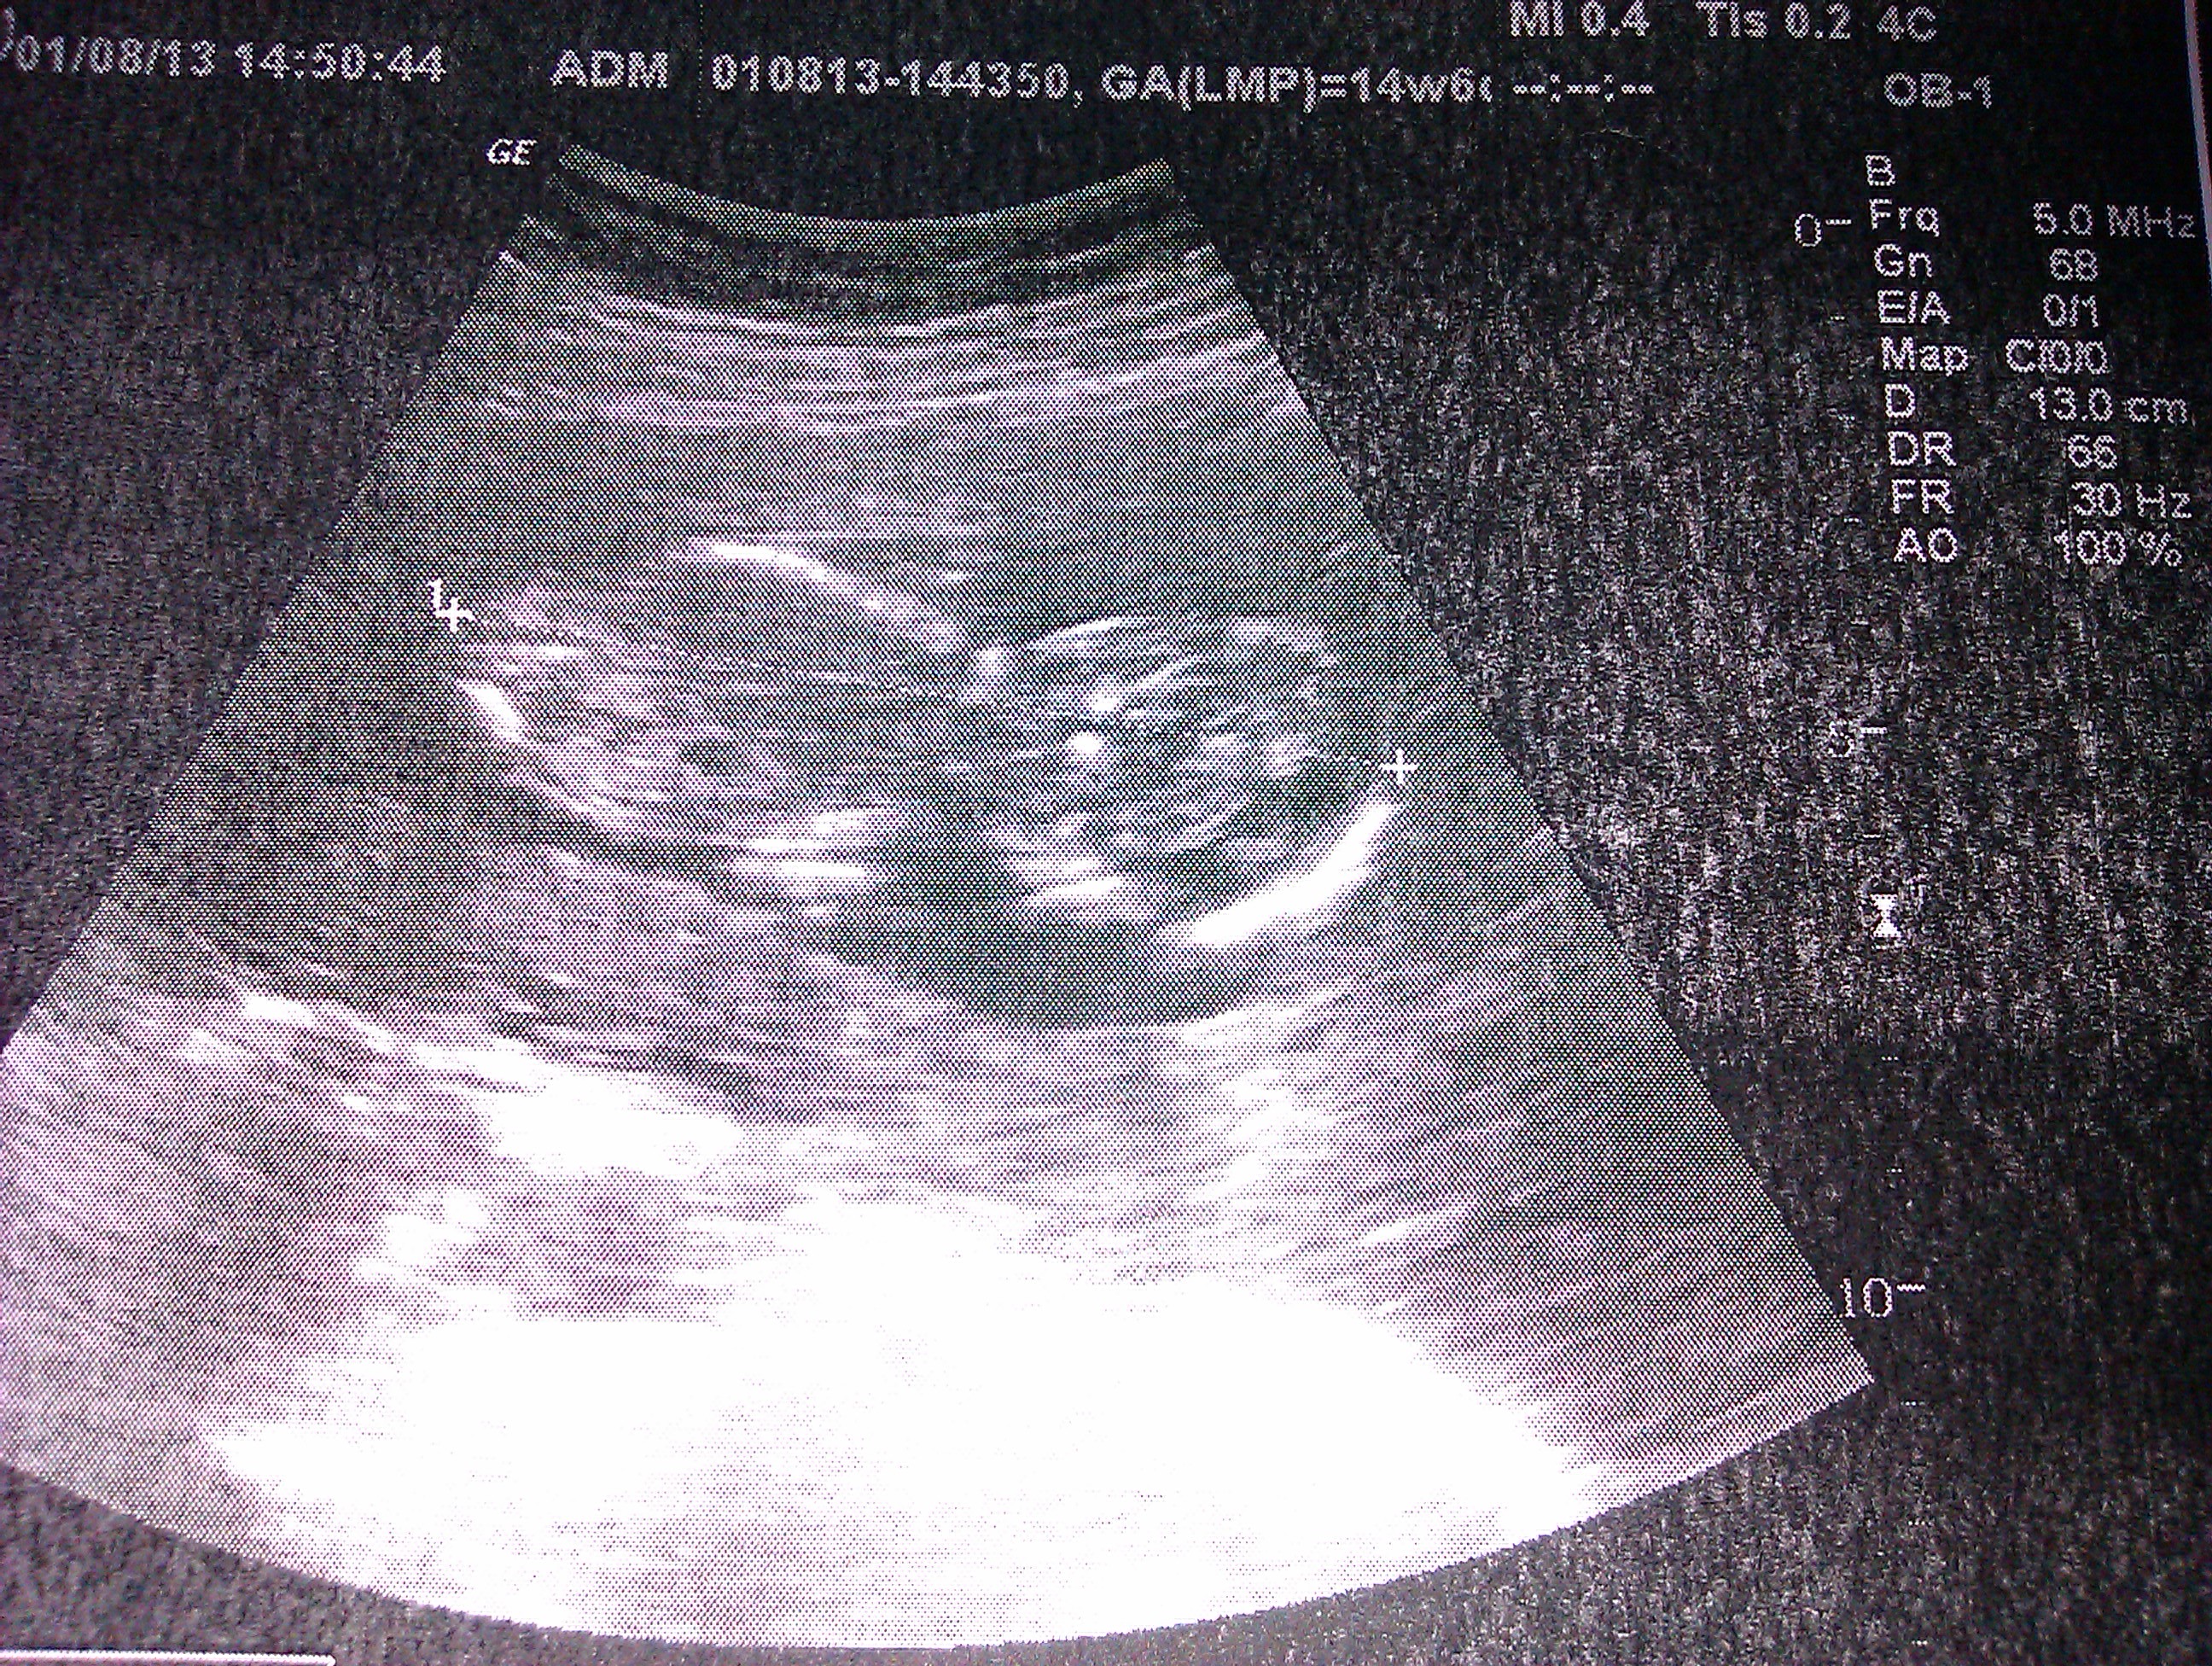

1. Finding out I was pregnant back in the spring! I had been trying to convince hubby to go for a second child for what seemed like forever and then, last spring, it happened! We had had a bad experience with our first, reflux, postnatal depression, countless sleepless nights so the fact that he decided to leave all that behind and go for it for a second time made me love and admire him even more!